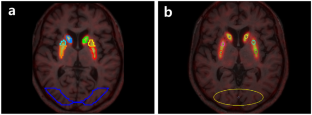

Fifteen ET (68.9 ± 6.6 years) and 10 PD patients (70.5 ± 6.3 years; Hoehn and Yahr stage, 2.3 ± 0.8) underwent two [18F]FP-CIT PET/CT scans with an interval of 48 ± 7 day. For both the test and retest studies, standardized uptake value ratios were estimated for 90-min and 3-h acquisitions for the caudate, anterior putamen, and posterior putamen using T1-MRI-based normalization (automatic) and fixed-VOI (manual) methods, with the occipital lobe as a reference. Reproducibility was evaluated by the bias, variability, percent test–retest, within-subject coefficient of variation, repeatability coefficient, and intraclass correlation coefficient (ICC).

Reproducibility was excellent, with low variability (ET: 6.99–8.02%, PD: 3.51–6.94%) and high reliability (ICC; ET: 0.88–0.96, PD: 0.98–0.99). The ET group showed higher variability and lower ICCs than the PD group. The variability in the 90-min images (ET: 7.85–8.59%, PD: 1.52–2.75%) was comparable to that in the 3-h images (ET: 6.99–8.02%, PD: 3.51–6.94%). There were no differences in variability among the subregions in the ET group. In the PD group, the variability was high in the posterior putamen (automatic method: 6.94%, manual method: 11.80%). The test–retest variability and ICCs were similar for the manual and automatic methods.